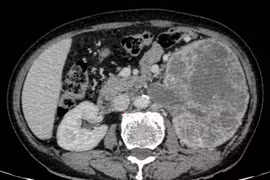

Tiểu máu, bụng chướng nhẹ phát hiện u thận khổng lồ xâm lấn đài bể thận

Các triệu chứng như đau hông lưng, đái máu, bụng to bất thường cần được thăm khám chuyên khoa sớm, giúp tăng khả năng phẫu thuật triệt căn, giảm biến chứng...